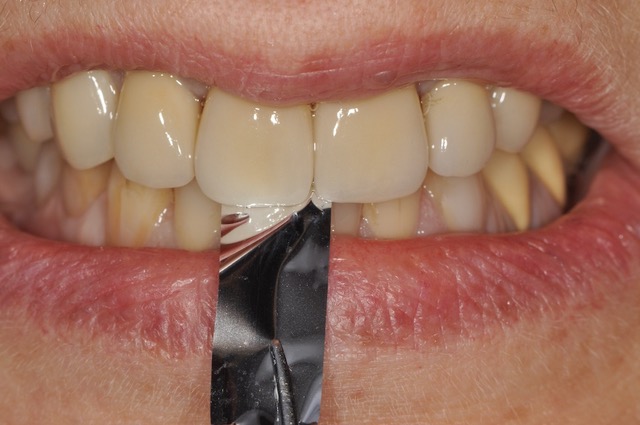

Fig. 8a à 8j : Résultat final

Un soin tout particulier doit être apporté à l’équilibration occlusale. L’équilibre occlusal est assuré, en OIM, par des contacts bilatéraux, simultanés et d’égale intensité sur les dents postérieures de canines à deuxièmes molaires (Fig. 9a et 9b). Les rapports inter-incisifs en OIM doivent laisser échapper une feuille de 9 microns d’épaisseur (Fig. 9c). Les entrées et sorties de cycle masticatoires sont contrôlés par élimination des interférences entre les versants cuspidiens des dents postérieures d’une part, et des faces palatines des incisives maxillaires et les bords libres des incisives mandibulaires d’autre part.

AVANT/APRÈS :